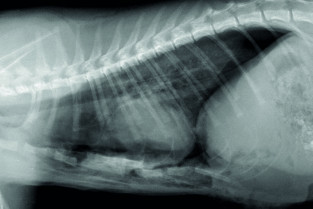

Le GEIM vous propose une séance de travaux pratiques de radiographies sur le thorax. Tous les aspects sont abordés sous la forme de TP de lecture de radiographies numériques sur station de travail sur tablettes (deux vétérinaires maximum par tablettes).

- adopter une méthodologie pour interpréter les affections pulmonaires chez les carnivores domestiques ;

- décrire l’aspect normal et anormal des poumons chez les carnivores domestiques.